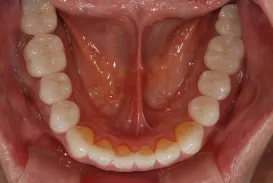

初診時

治療完了時

| 患者様のお悩み | 咀嚼障害(左下奥歯) |

|---|---|

| 治療法・使用素材 | 自家歯牙移植治療 |

| 患者様の年代 | 30代 |

| 治療開始年齢 | 30代 |

| 治療にかかった期間 | 6か月 |

| 性別 | 女性 |

| この治療のリスクについて | 移植歯が生着するかどうか |

| 治療にかかった費用 | 5万円 |